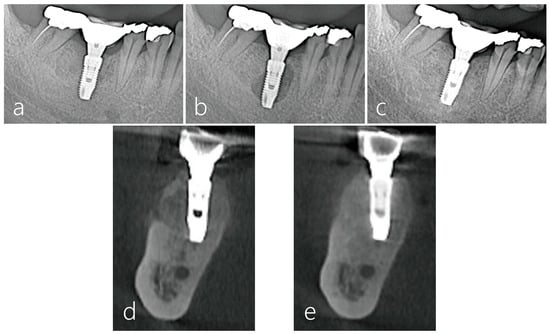

2.4. Surgical Reentry

2.6. Radiographic Evaluation

3. Result